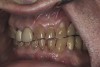

(6.) Preoperative right lateral, open view.

Figure 6

(7.) Preoperative anterior, open view. Note the significant amount of wear, erosion, and abfraction lesions.

Figure 7

(9.) Preoperative right lateral, closed view.

Figure 9

(10.) Preoperative anterior, closed view. Note the end-to-end occlusion of the anterior teeth and the wear on the incisors and centrals resulting in no anterior or canine guidance.

Figure 10

(11.) Preoperative left lateral, closed view.

Figure 11

(12.) Preoperative right anterior, close-up view.

Figure 12

(13.) Preoperative anterior, close-up view.

Figure 13

(14.) Preoperative left anterior, close-up view.

Figure 14